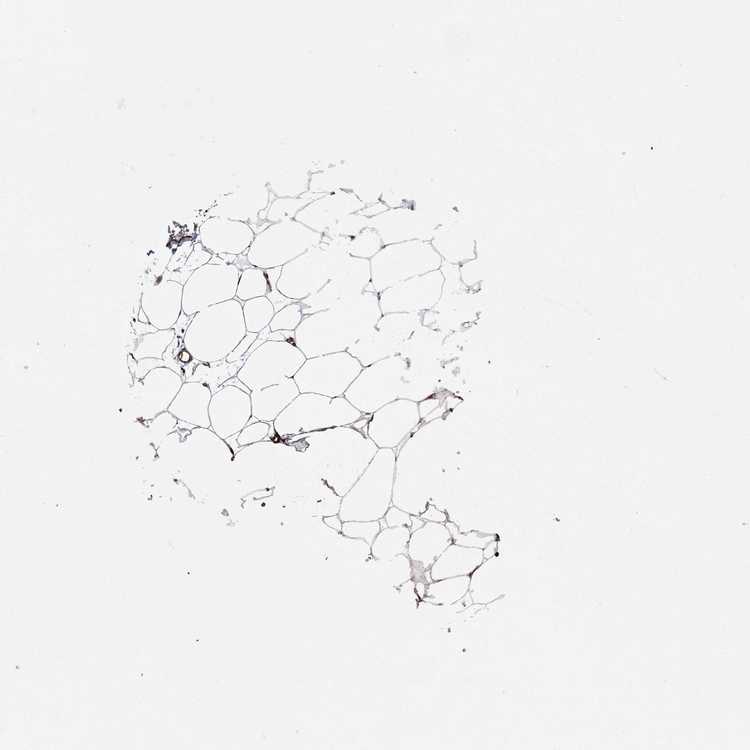

BREAST - Antibody stainingi

Antibody staining in the annotated cell types in the current human tissue is reported as not detected, low, medium, or high, based on conventional immunohistochemistry profiling in selected tissues. This score is based on the combination of the staining intensity and fraction of stained cells.

Each image is clickable and will lead to virtual microscopy that enables deeper exploration of all samples and also displays staining intensity scores, fraction scores and subcellular localization as well as patient and tissue information for each sample.

Antibody HPA038619Antibody HPA058231

Adipocytes MediumNot detected

Glandular cells HighHigh

Myoepithelial cells MediumMedium